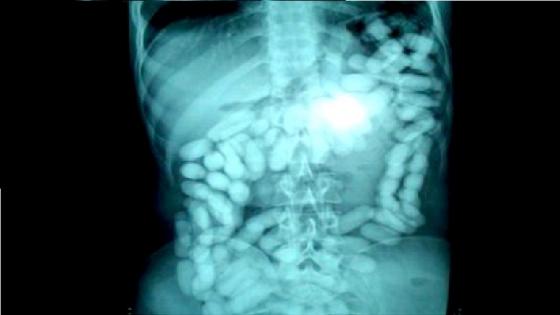

وأضاف البلاغ، أنه تم الاحتفاظ بالمشتبه فيه تحت المراقبة الطبية بالمستشفى الجامعي ابن رشد بغرض استخراج الكبسولات من أمعائه، والتي أسفرت في النهاية عن حجز الكمية المذكورة من مخدر الكوكايين على شكل 75 كبسولة.